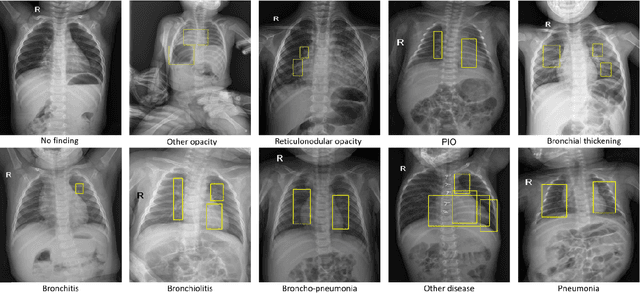

Abstract:Chest radiograph (CXR) interpretation in pediatric patients is error-prone and requires a high level of understanding of radiologic expertise. Recently, deep convolutional neural networks (D-CNNs) have shown remarkable performance in interpreting CXR in adults. However, there is a lack of evidence indicating that D-CNNs can recognize accurately multiple lung pathologies from pediatric CXR scans. In particular, the development of diagnostic models for the detection of pediatric chest diseases faces significant challenges such as (i) lack of physician-annotated datasets and (ii) class imbalance problems. In this paper, we retrospectively collect a large dataset of 5,017 pediatric CXR scans, for which each is manually labeled by an experienced radiologist for the presence of 10 common pathologies. A D-CNN model is then trained on 3,550 annotated scans to classify multiple pediatric lung pathologies automatically. To address the high-class imbalance issue, we propose to modify and apply "Distribution-Balanced loss" for training D-CNNs which reshapes the standard Binary-Cross Entropy loss (BCE) to efficiently learn harder samples by down-weighting the loss assigned to the majority classes. On an independent test set of 777 studies, the proposed approach yields an area under the receiver operating characteristic (AUC) of 0.709 (95% CI, 0.690-0.729). The sensitivity, specificity, and F1-score at the cutoff value are 0.722 (0.694-0.750), 0.579 (0.563-0.595), and 0.389 (0.373-0.405), respectively. These results significantly outperform previous state-of-the-art methods on most of the target diseases. Moreover, our ablation studies validate the effectiveness of the proposed loss function compared to other standard losses, e.g., BCE and Focal Loss, for this learning task. Overall, we demonstrate the potential of D-CNNs in interpreting pediatric CXRs.